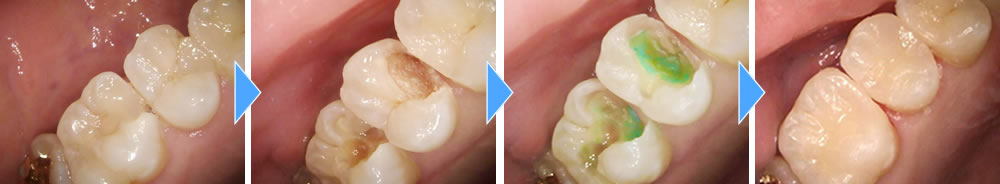

歯の内部まで進行した虫歯を除去しセラミックインレーで治療した症例

年齢

20代

性別

女性